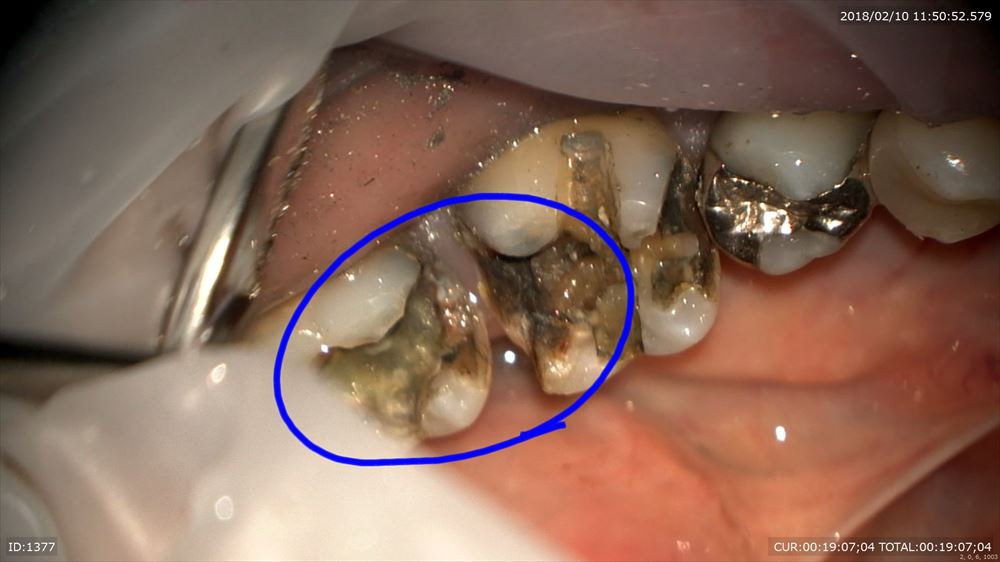

銀歯虫歯の方。

銀歯の中は

こうなっています。

これもマイクロスコープを使用し無痛で感染除去 MTAで

これで型とり。大丈夫!!